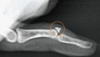

This image shows a herniation at which level L1/L2 L2/L3 L3/L4 L4/L5 L5/S1

**L4/L5**